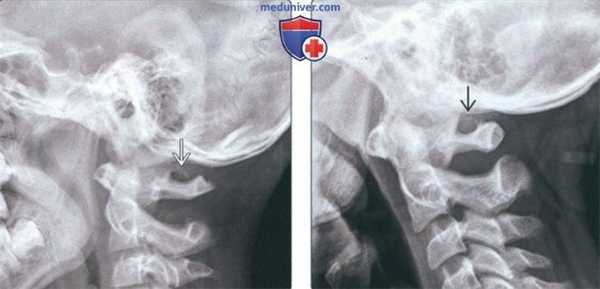

(Слева) На рентгенограмме верхних шейных позвонков в боковой проекции определяется незамкнутая костная дуга над отверстием позвоночной артерии в С1, типичная для аномалии Киммерле (неполный вариант).

(Справа) На рентгенограмме верхних шейных позвонков в боковой проекции визуализируется замкнутая костная дуга над отверстием позвоночной артерии в С1, характерная для классической аномалии Киммерле (полный вариант).